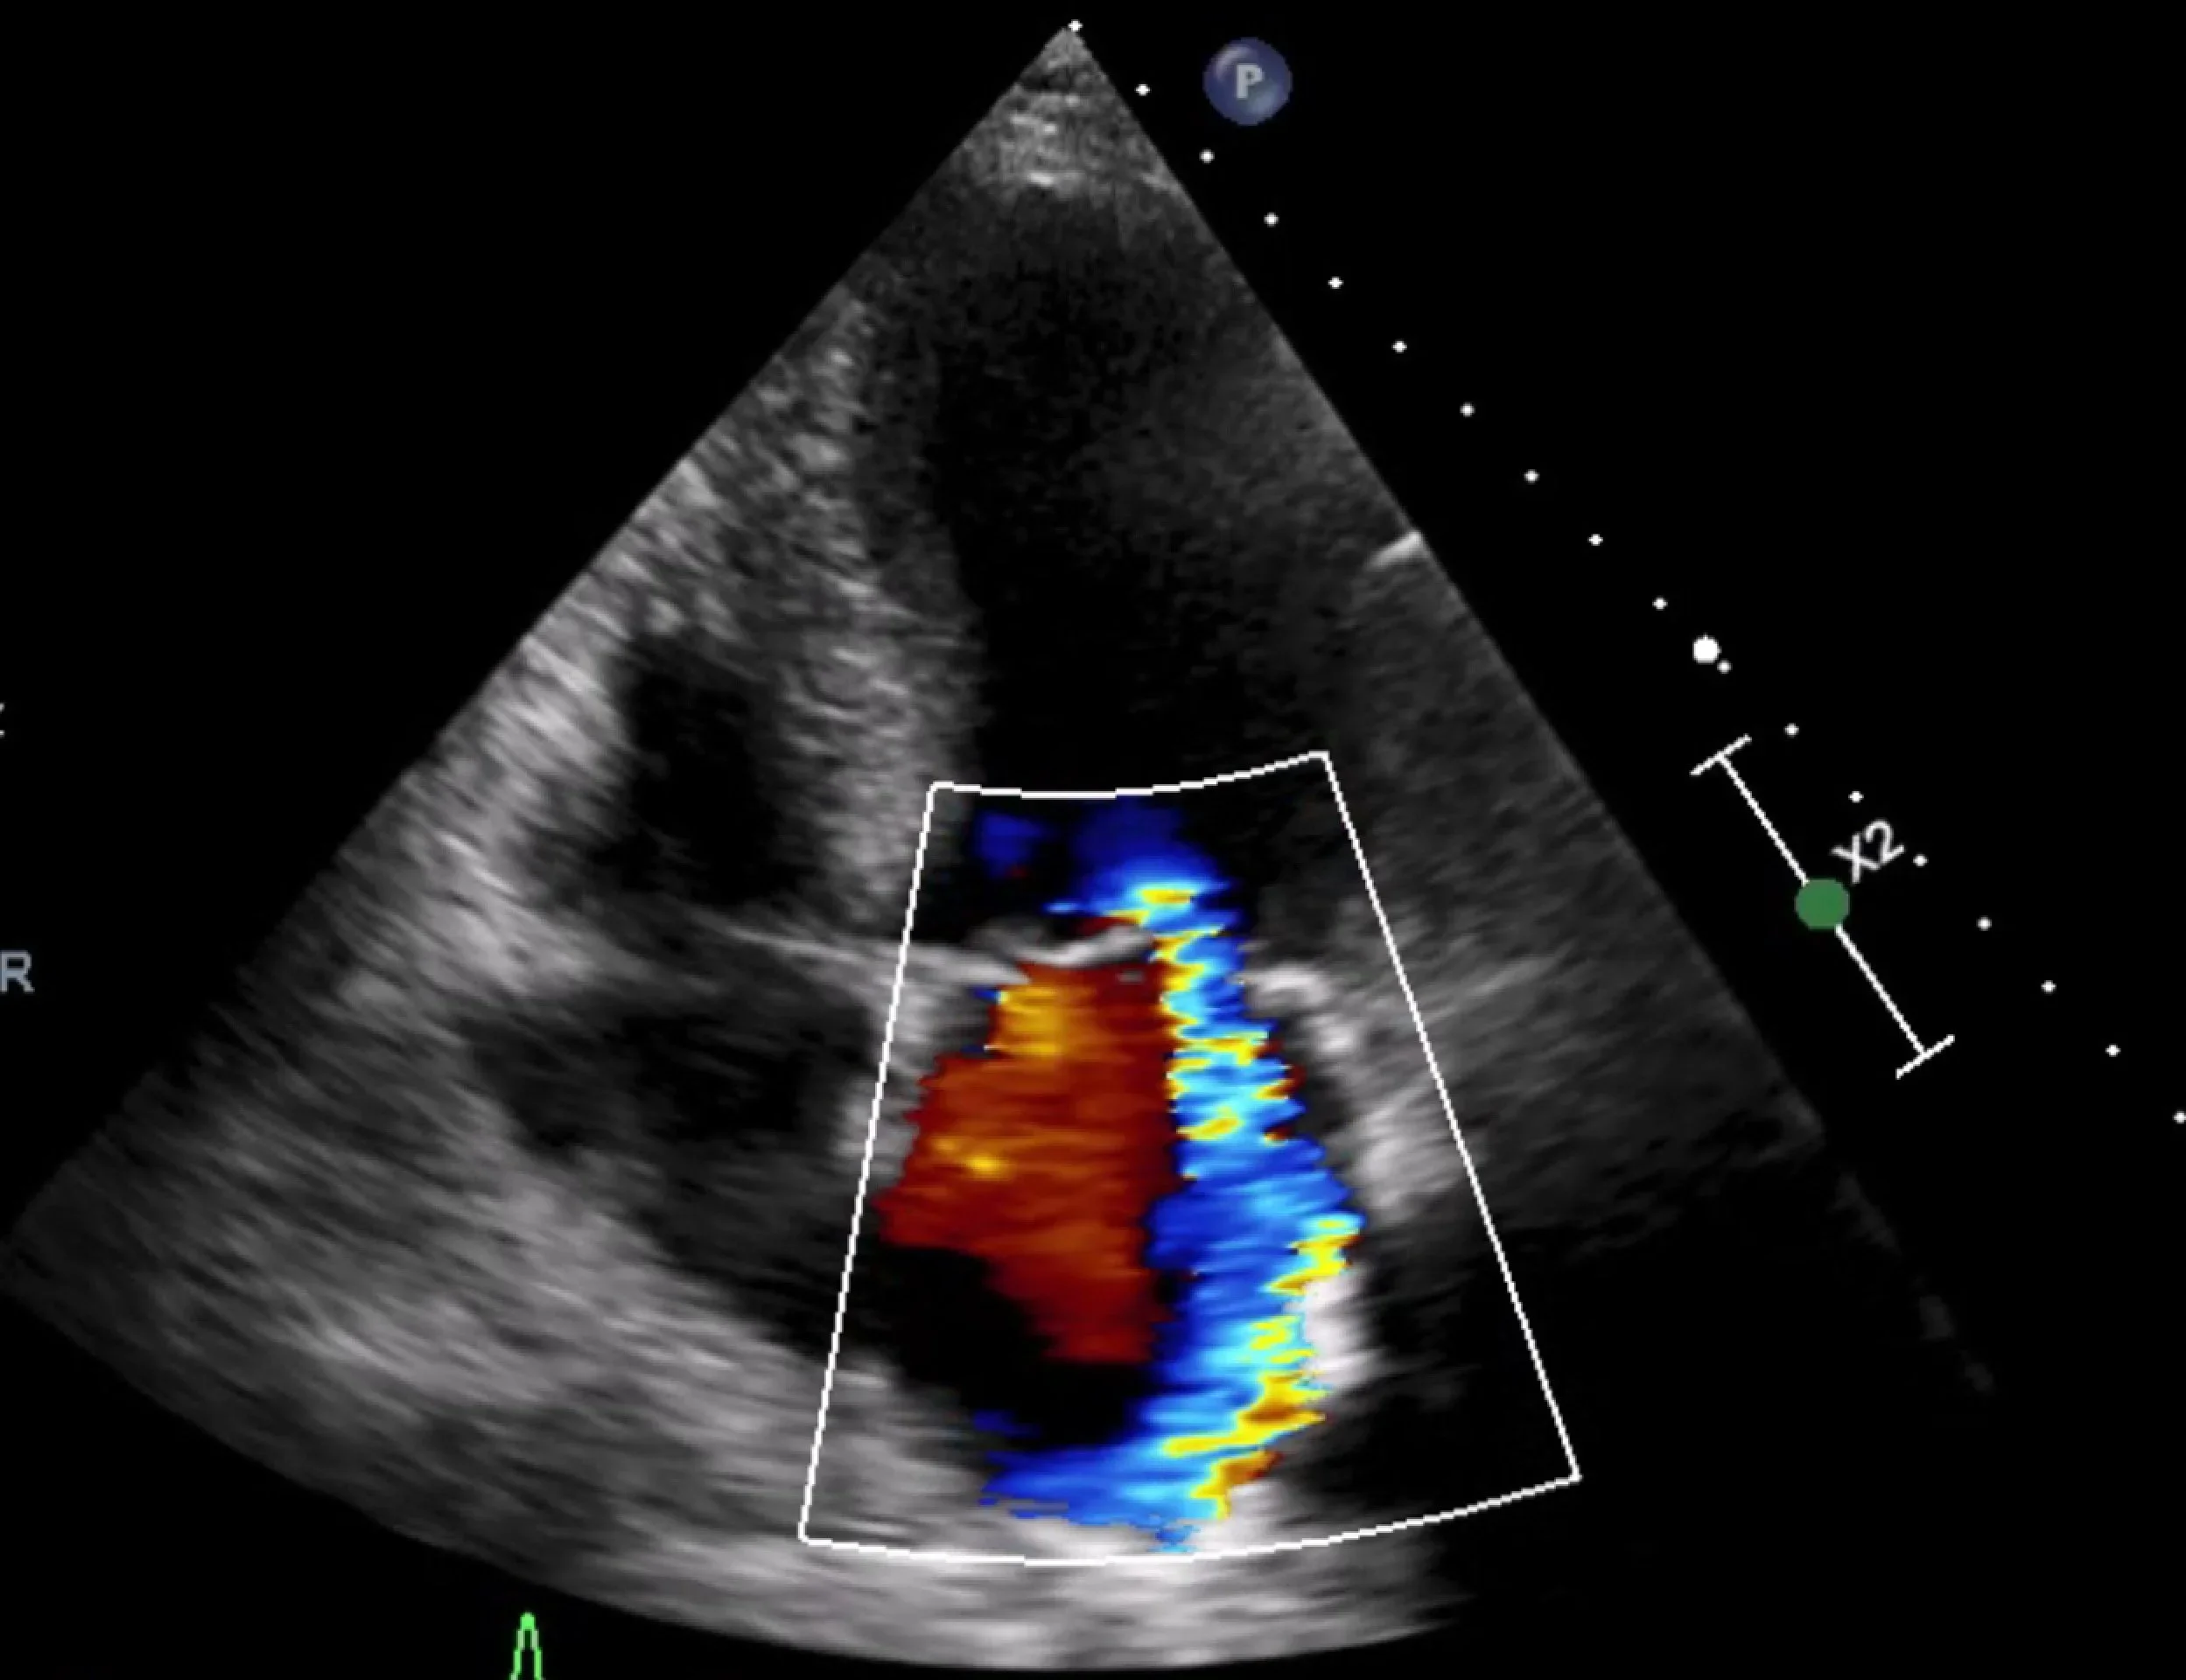

Ultrasound image of a heart showing color Doppler flow including red and blue signals indicating blood flow direction and velocity.

The key test is an echocardiogram (ultrasound of the heart), which assesses valve structure and severity and how the heart is coping.